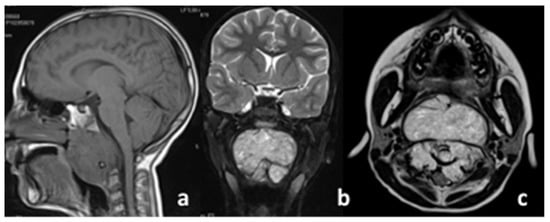

The patient was a 10-year-old female with a severe occlusion in the upper airways (highlighted by an urgent first MRI) due to a bulky expansive lesion with net margins involving nearly the whole clivus area, extending up to C2–C3. The lesion studied in the morphological T1/T2-weighted sequences presented hyperintense, non-homogenous characteristics in T2 (see Figure 1b,c) and an isointense appearance in T1 (see Figure 1a), with intense enhancement after administration of the contrast medium.

Figure 1. Imaging at diagnosis: (a) sagittal view, (b) coronal view, (c) axial view.

The classic chordoma in MRI is iso/hypointense in the T1-weighted images but typically hyperintense in the T2-weighted images, this being due to their increased water component. This can also be associated with mucous, hemorrhages, and calcification. Lobular aspects and multiple hypo-intense septa that are connected to areas of necrosis or cartilage were present in this case.